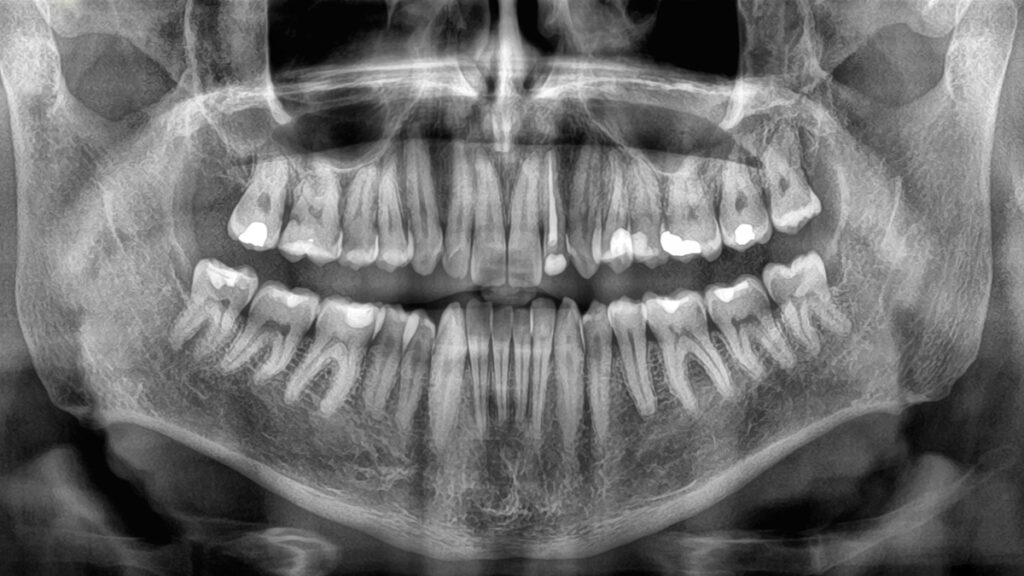

How quickly we lose teeth in old age has been linked to a heightened risk of mortality, according to a comprehensive new study. This research underscores the importance of maintaining good oral health and suggests that tooth loss could serve as a critical indicator of other serious health issues.

Previous studies have established a connection between tooth loss and mortality, generally indicating that fewer teeth correlate with a greater chance of earlier death. However, until now, there has been limited data on how the speed of tooth loss might affect this association. A team of researchers from Sichuan University in China sought to fill this gap by examining tooth loss in 8,073 elderly individuals, tracking their rate of tooth loss against mortality over an average period of 3.5 years.

The study found that among older adults, the risk of all-cause mortality significantly increased with a more rapid progression of tooth loss, irrespective of the initial number of teeth. This relationship persisted even after adjusting for various factors known to influence health and disease, such as sex, age, education level, drinking habits, and exercise frequency.

Importantly, the researchers are not suggesting that tooth loss itself is fatal. Rather, they propose that the health issues leading to tooth loss may also be contributing to a shortened lifespan. Therefore, tooth loss could be utilized as a marker to assess an individual’s overall health and mortality risk.